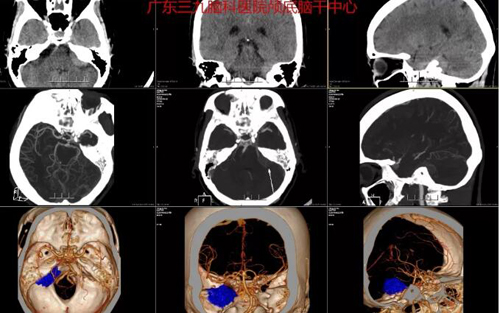

图1:术前CTA示左侧桥小脑角区示一占位性病变,其内示少许细小血管影,周围血管受压呈弧形;脑动脉粥样硬化改变。